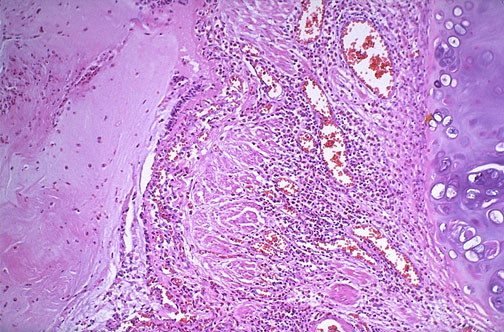

| Between the bronchial cartilage at the right and the bronchial lumen filled with mucus at the left is a submucosa widened by smooth muscle hypertrophy, edema, and inflammation (mainly eosinophils). These are changes of bronchial asthma, more specifically extrinsic asthma from type I hypersensitivity to allergens. The peripheral eosinophil count or the sputum eosinophils can be increased during an asthmatic attack. |